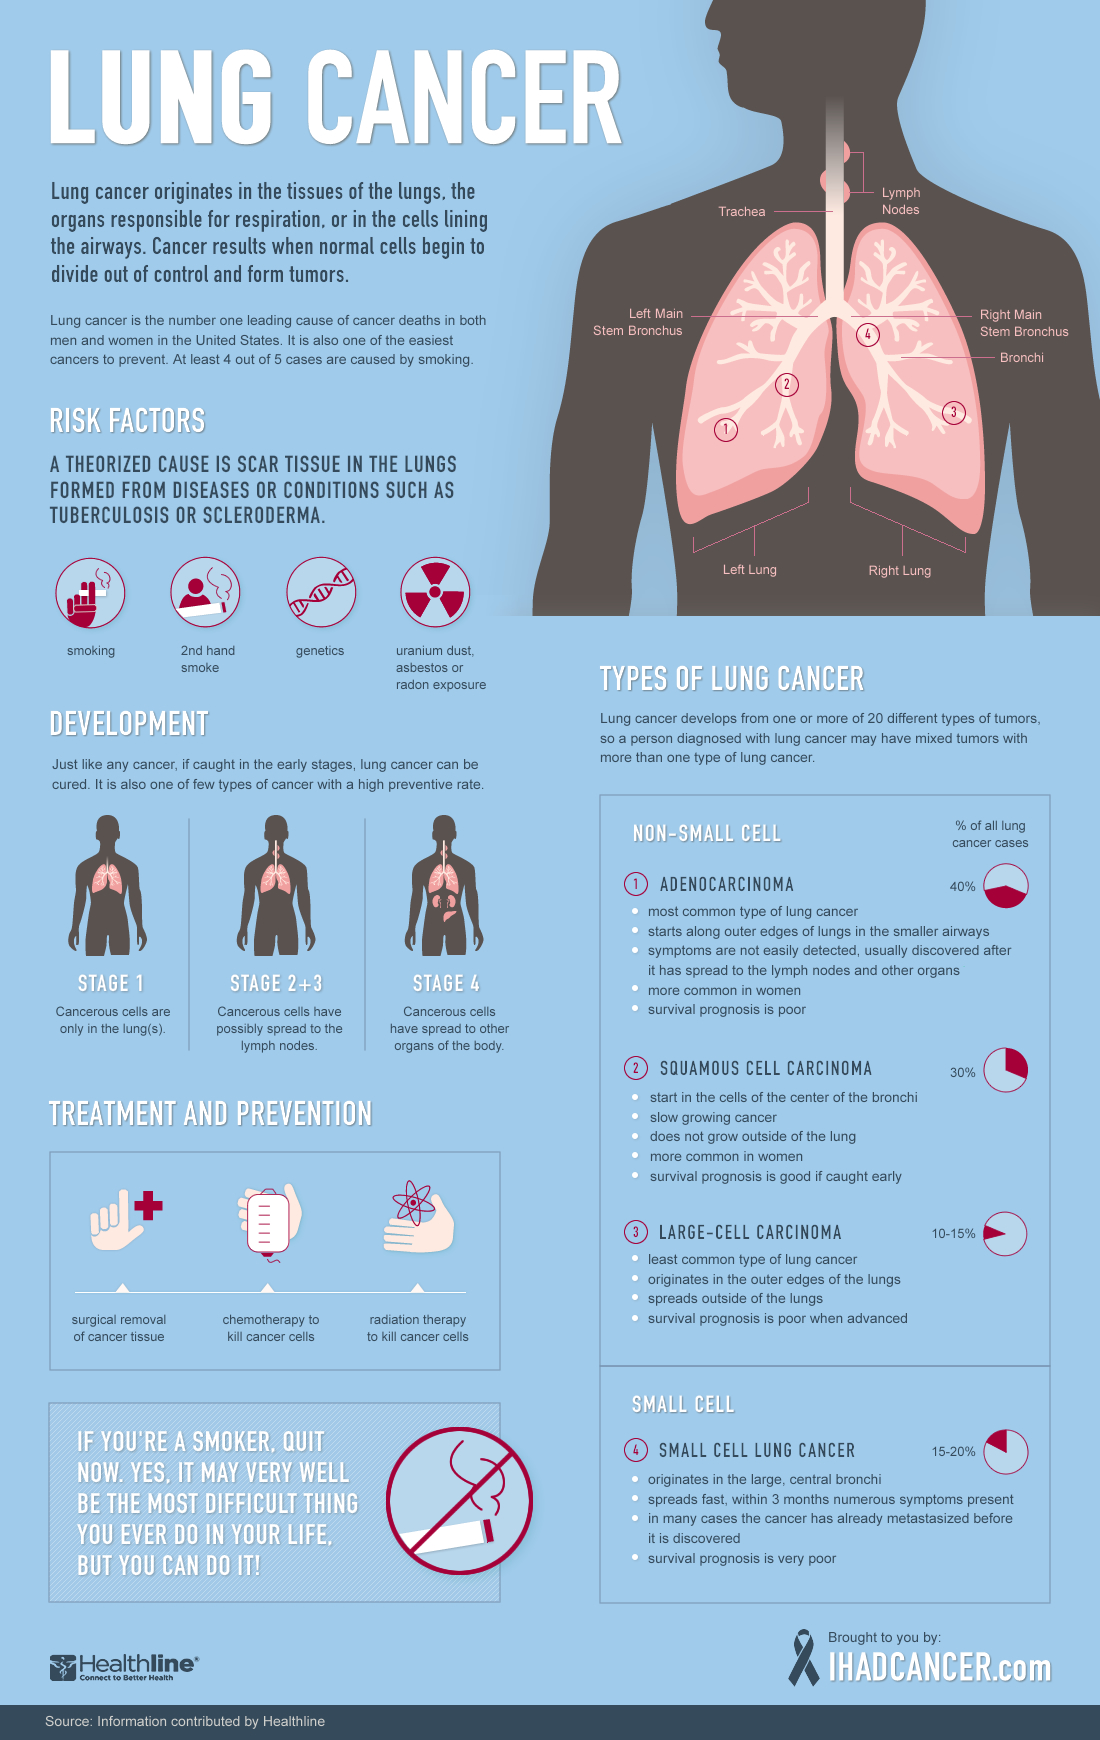

Staying active may help prevent certain cancers. Lung cancer is one of the most common cancers and has one of the lowest survival rates in the world. Excess weight results in the production and circulation of more.

Lung cancer is cancer that starts in your lungs. The most important thing you can do to prevent lung cancer is to not start smoking, or to quit if you smoke. Lung cancer patient and advocate jill feldman takes pills at home that shrink tumors by blocking a signal that tells cancer cells to grow.

People with small cell lung cancer are usually treated with radiation therapy and chemotherapy. Changing lifestyle or eating habits. It is the leading cause of cancer death among men and women.